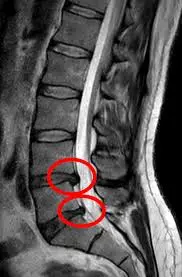

الانزلاق الغضروفي البسيط هو حالة طبية تحدث عندما يتحرك القرص الغضروفي الموجود بين الفقرات قليلاً من مكانه الطبيعي، مما يسبب ضغطاً خفيفاً على الأعصاب المحيطة، ويعمل هذا القرص كوسادة طبيعية تمتص الصدمات وتحمي العمود الفقري، وعندما يحدث انزلاق بسيط فيه، قد تشعر بألم أو تنميل في المنطقة المصابة.

يختلف الانزلاق البسيط عن الحالات الشديدة في أن الغضروف لا يخرج بشكل كامل من مكانه، بل يكون الضغط على الأعصاب محدودًا، وهذا يجعل فرص الشفاء التام ممتازة مع العلاج المناسب، ويقلل من احتمالية الحاجة إلى التدخل الجراحي. معظم المرضى الذين يعانون من هذه الحالة يتعافون تماماً خلال أسابيع قليلة باتباع خطة علاجية مناسبة.